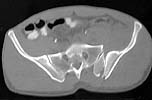

A woman in her 30's in a high speed MVC with this closed pelvic fracture. She's hemodynamically stable, no other injuries - belly, chest, and head are all fine. She also has a comminuted supracondylar femur fracture on the R side.

Preop CT

the enclosed ct image demonstrates her second, not upper sacral segment.

her plain pelvic radiographs indicate upper sacral dysmorphism, which has a significant impact on safe iliosacral screw insertion, regardless of imaging modality chosen to assist insertion.

the ct image reveals no significant posterior pelvic degloving injury, for that single axial image.

we need more ct info(images) to make appropriate therapeutic recommendations.

the strategy relies on the other images which reveal the exact iliac fracture-sacroiliac disruption sites, local soft tissue condition, as well as the upper sacral morphology.